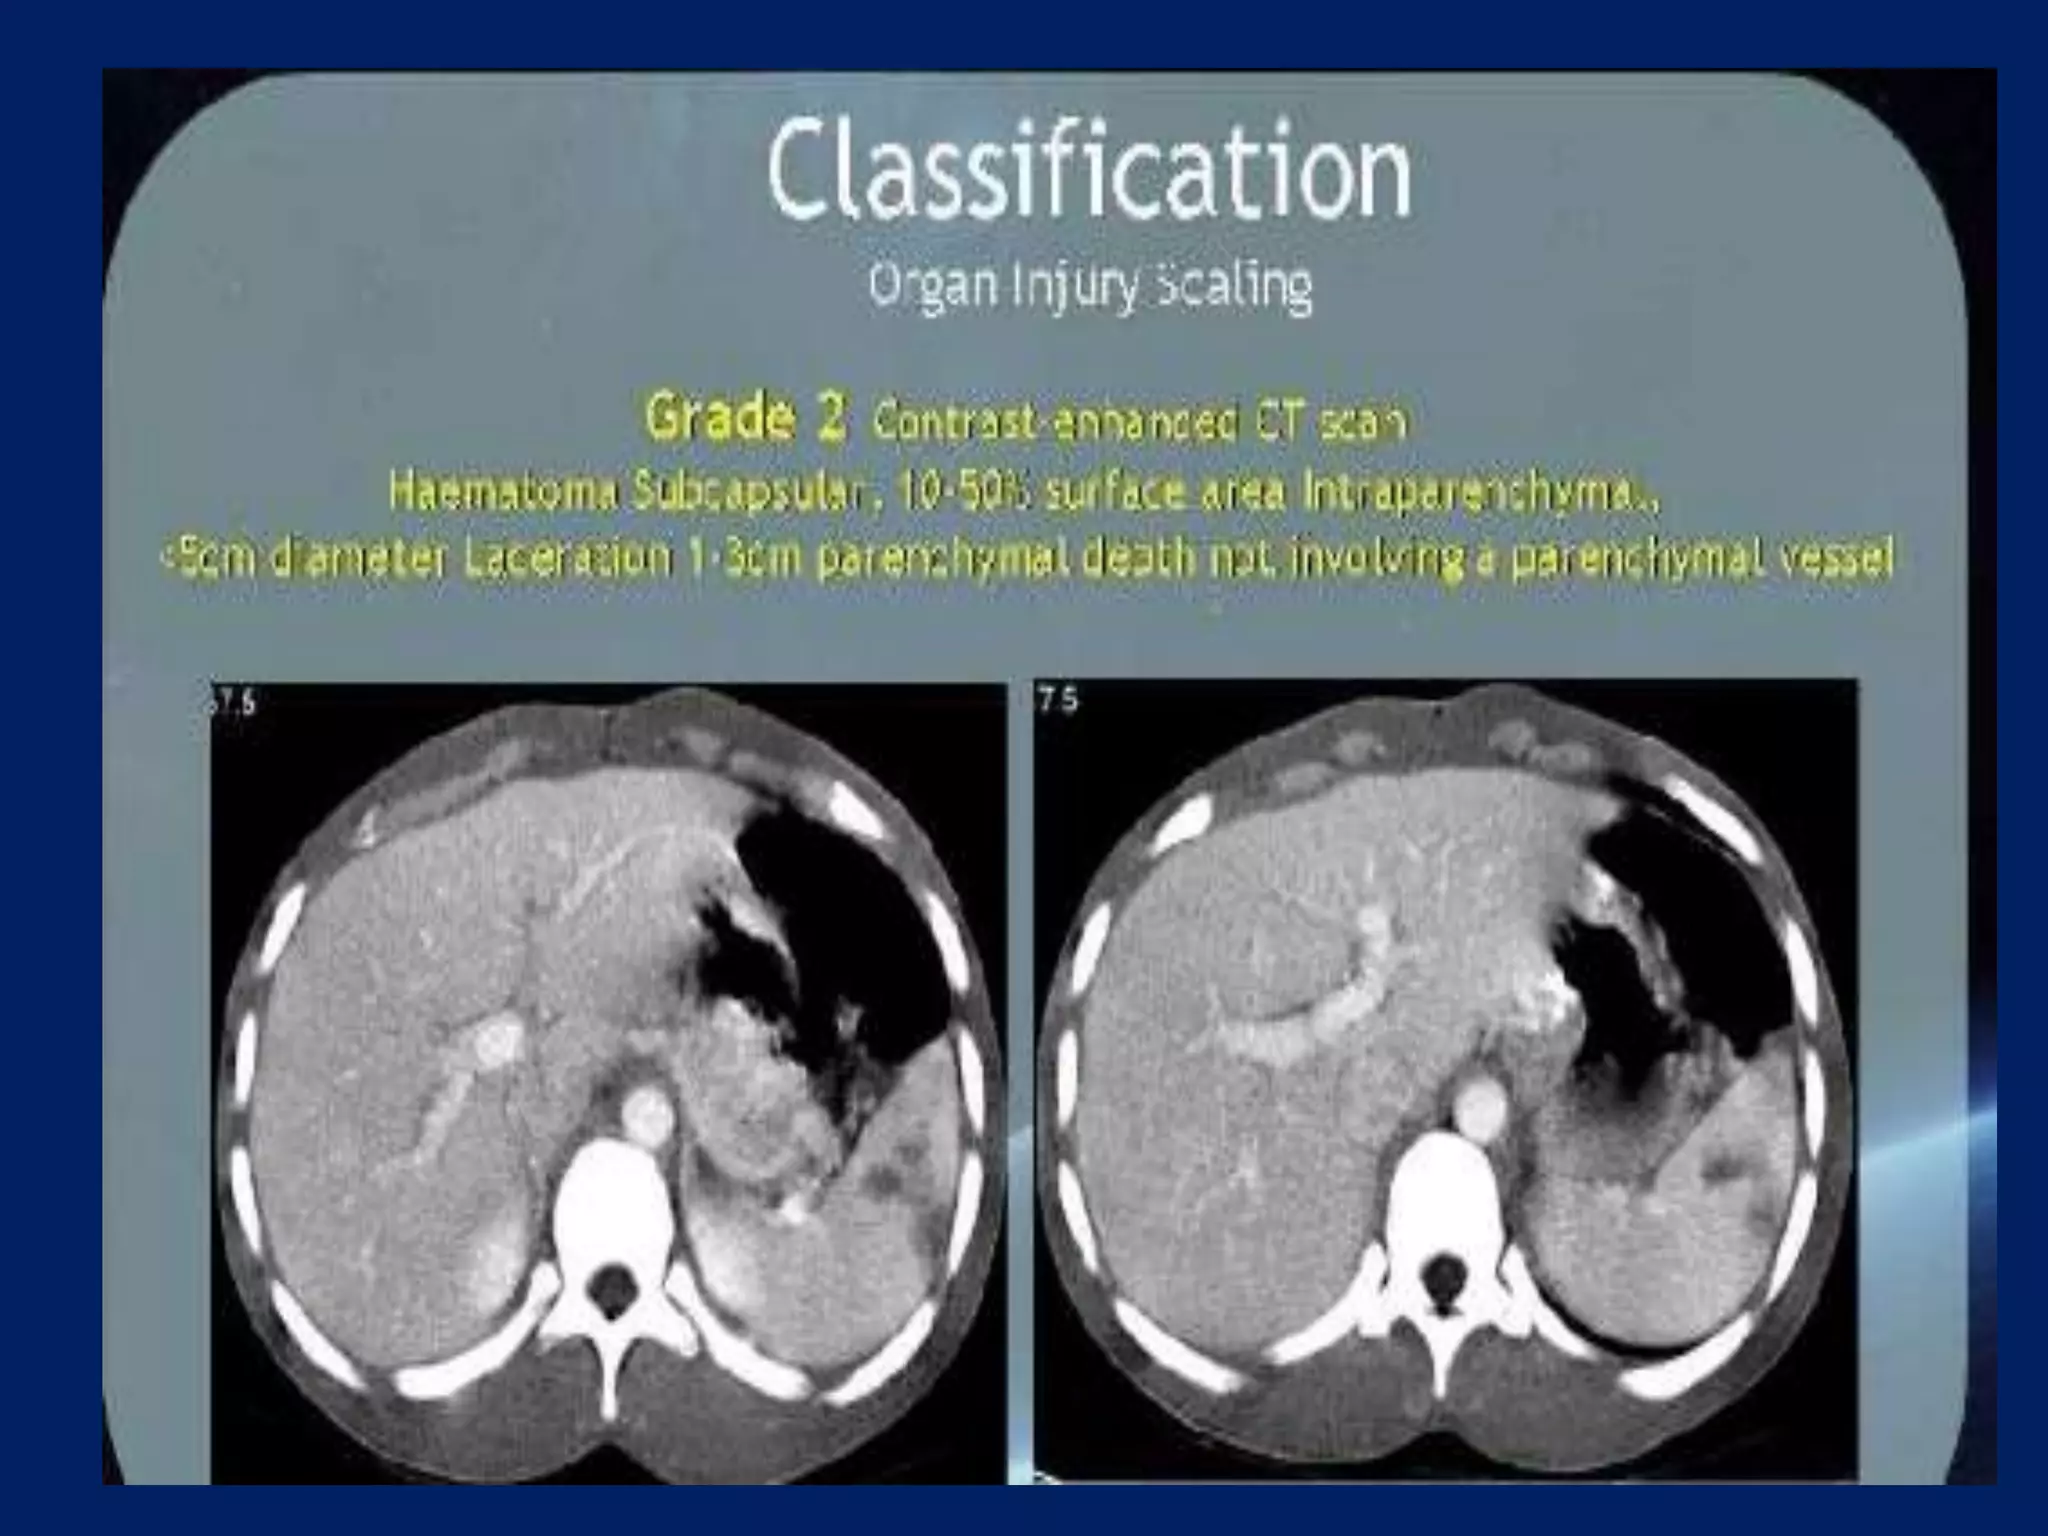

This document discusses imaging of the spleen and summarizes various congenital anomalies and pathologies that can affect the spleen. Some common congenital anomalies mentioned include accessory spleens, asplenia, polysplenia, and splenic fusions. Acquired conditions like repeated infarctions, infiltration, tumors, and cysts can also cause splenomegaly or functional asplenia. Wandering spleen is discussed as a rare congenital anomaly where the spleen lacks attachments and is mobile within the abdomen. Various grades of splenic lacerations and examples of splenic imaging findings are also briefly summarized.